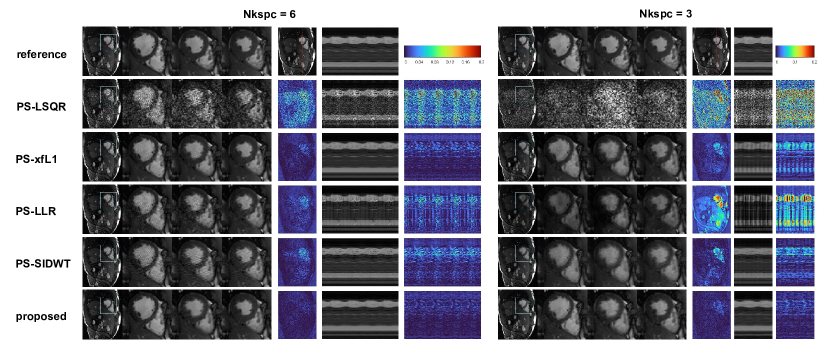

The reconstructed images of one data case using the best are displayed in Figure 7. Obviously, when Nkspc is reduced from 6 to 3, the reconstruction error deteriorates significantly. The images reconstructed by PS-LSQR model is totally corrupted by noise. The images reconstructed by PS-LLR model suffer from dark streaking artifacts on the M-mode motion profile, which implies that the image quality fluctuates from frame to frame. The image reconstructed by PS-xfL1 model displays better image quality, but residual dark streaks can still be observed from the M-mode images. The image reconstructed by PS-SIDWT model displays severe smoothing effects on the M-mode images, where the atrium motion profile is blurred. Scattered noise can be perceived on the images reconstructed by PS-xfL1 and PS-SIDWT method. In comparison, the proposed method produces the best visual image quality and the clearest motion profile. Obviously the reconstruction error level of the proposed method is the lowest among all the models, and the error distribution is also more uniform across the image.

5.3 Prospective Experiments

The reconstructed images of one volunteer are shown in Figure 8. The results are consistent with the retrospective experiment, with only slight differences. Under Nkspc=18, all the regularized PS model algorithms have similarly good image quality. However, the image reconstructed by PS-LSQR method is obviously worse than other methods. When Nkspc is further reduced to 9 and 6, the performance of PS-LSQR deteriorates very quickly, while other methods can still maintain relatively good image quality. When Nkspc is reduced to 3, the images reconstructed by PS-LSQR are totally corrupted by noise, PS-LLR method becomes very unstable, the reconstructed images suffer from darkening artifacts. The images reconstructed by PS-SIDWT model are blurred at the blood-myocardium boundary. The images reconstructed by PS-xfL1 model and the proposed method have similar image quality. However, the proposed method is nearly 20-fold faster than the PS-xfL1 algorithm. The zoomed images of another volunteer are shown in Figure 9. The proposed method achieves good image quality and the fastest reconstruction speed simultaneously.